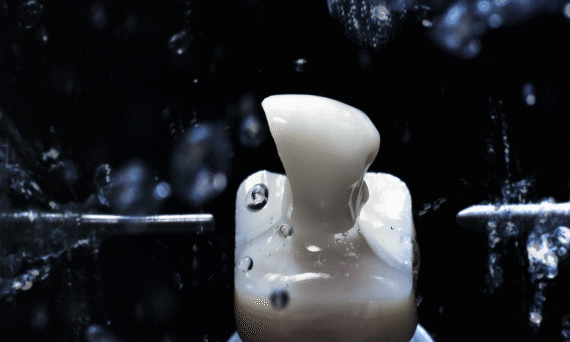

德国3Shape数字化口腔扫描能够让患者轻松舒适地躺在牙椅上配合医生采集口腔数据,仅需十多分钟,就能获得1:1重建的数字化口腔模型。

只需几分钟,就能完成患者牙齿数据的搜集并同步到电脑上,这样患者和医生能一同看到自己口内的全息影像,且还原得十分真实。

传统制作牙冠需要取模、切削、烧结、上瓷、上釉等8个步骤,一个环节错误就会导致数据失准,出现误差,现在通过数字化CAD/CAM设备,精确到微米,制作假牙的时间可以提速到2小时,就能完成最终戴牙,修复效率大大提高。

一整套的数字化设备可以让患者能够实现当天种植,当天带牙,当天就能吃苹果。